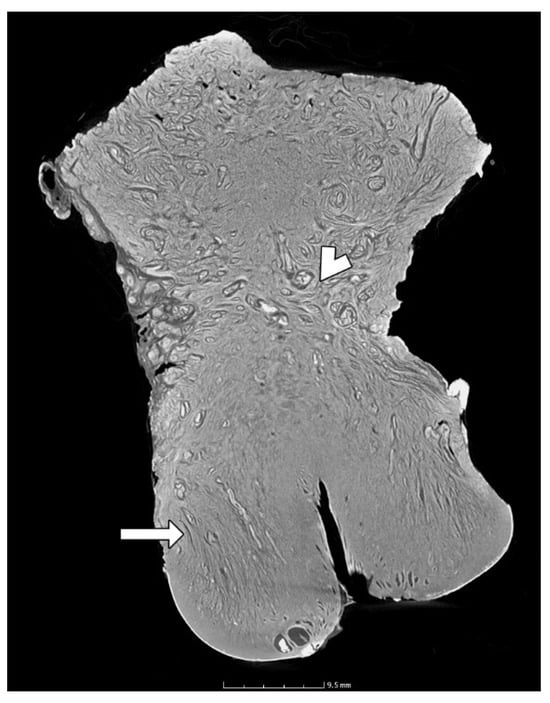

3.3. The Anatomy of the Uterine Cervix

3.6. The Endocervical Canal Beyond the External os